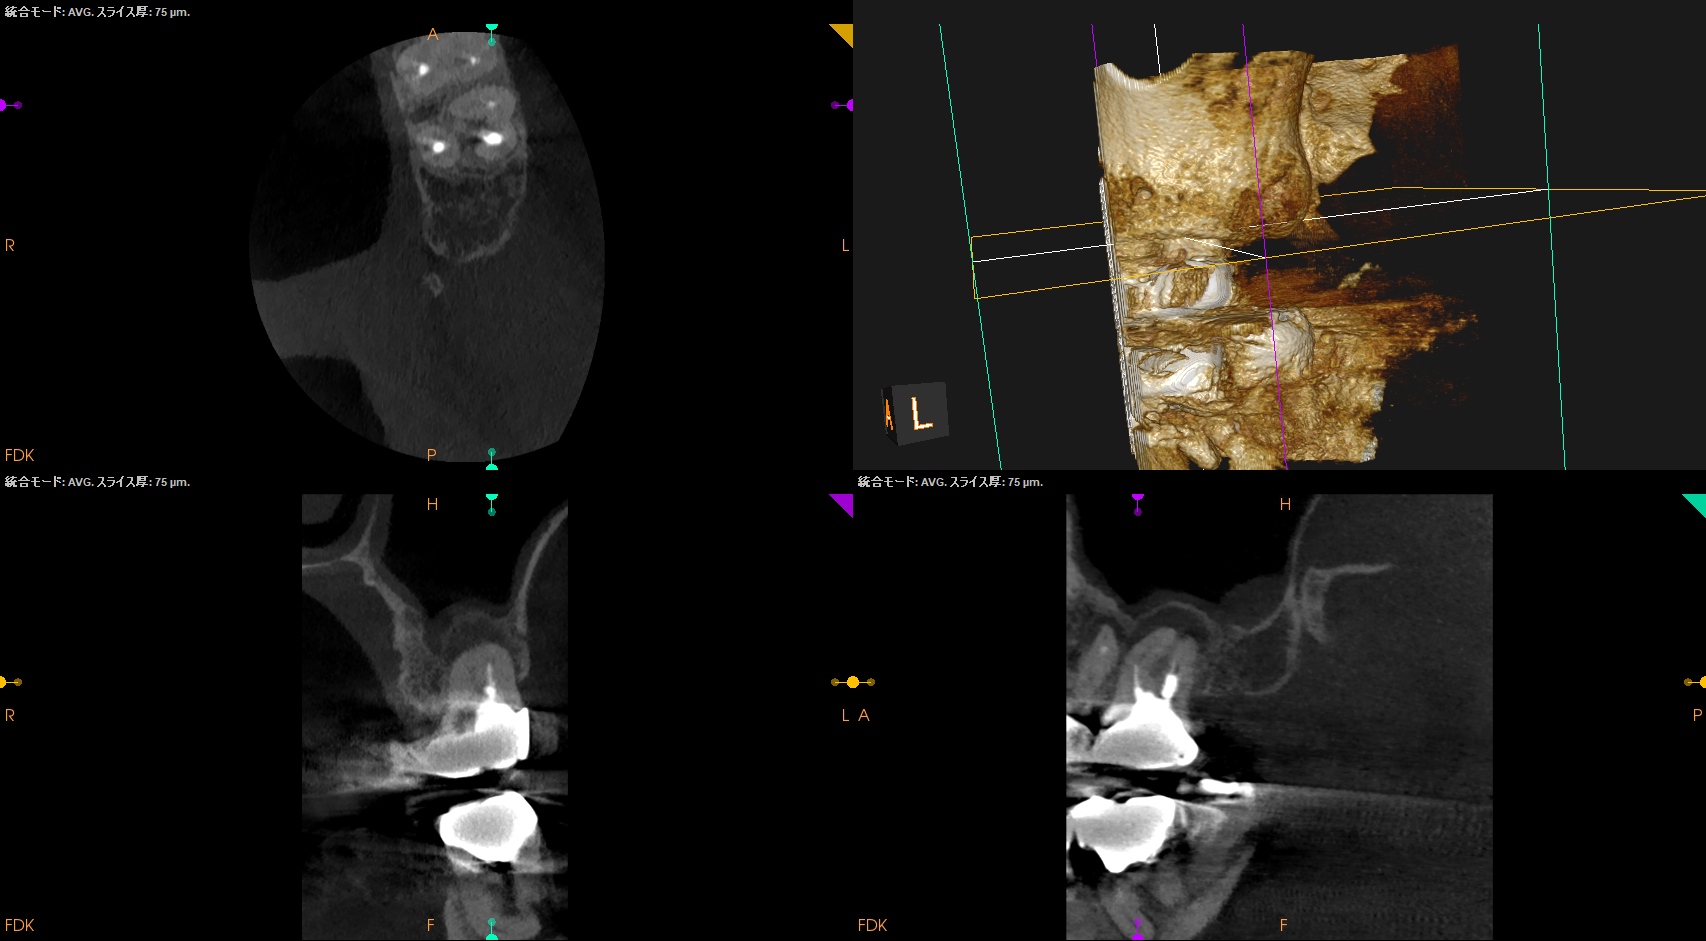

この臨床的事実をなんとかCBCTを使用して明らかにできないだろうか?と私は常々考えてきた。

今日はCaseを通じてそれを示してみたい。

術後のPA, CBCTは以下である。

MB1

MB2

DB

P

問題はないだろう。